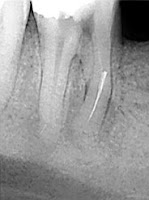

- Presencia de instrumentos rotos dentro del conducto

Instrumento roto dentro del conducto Sobreobturación